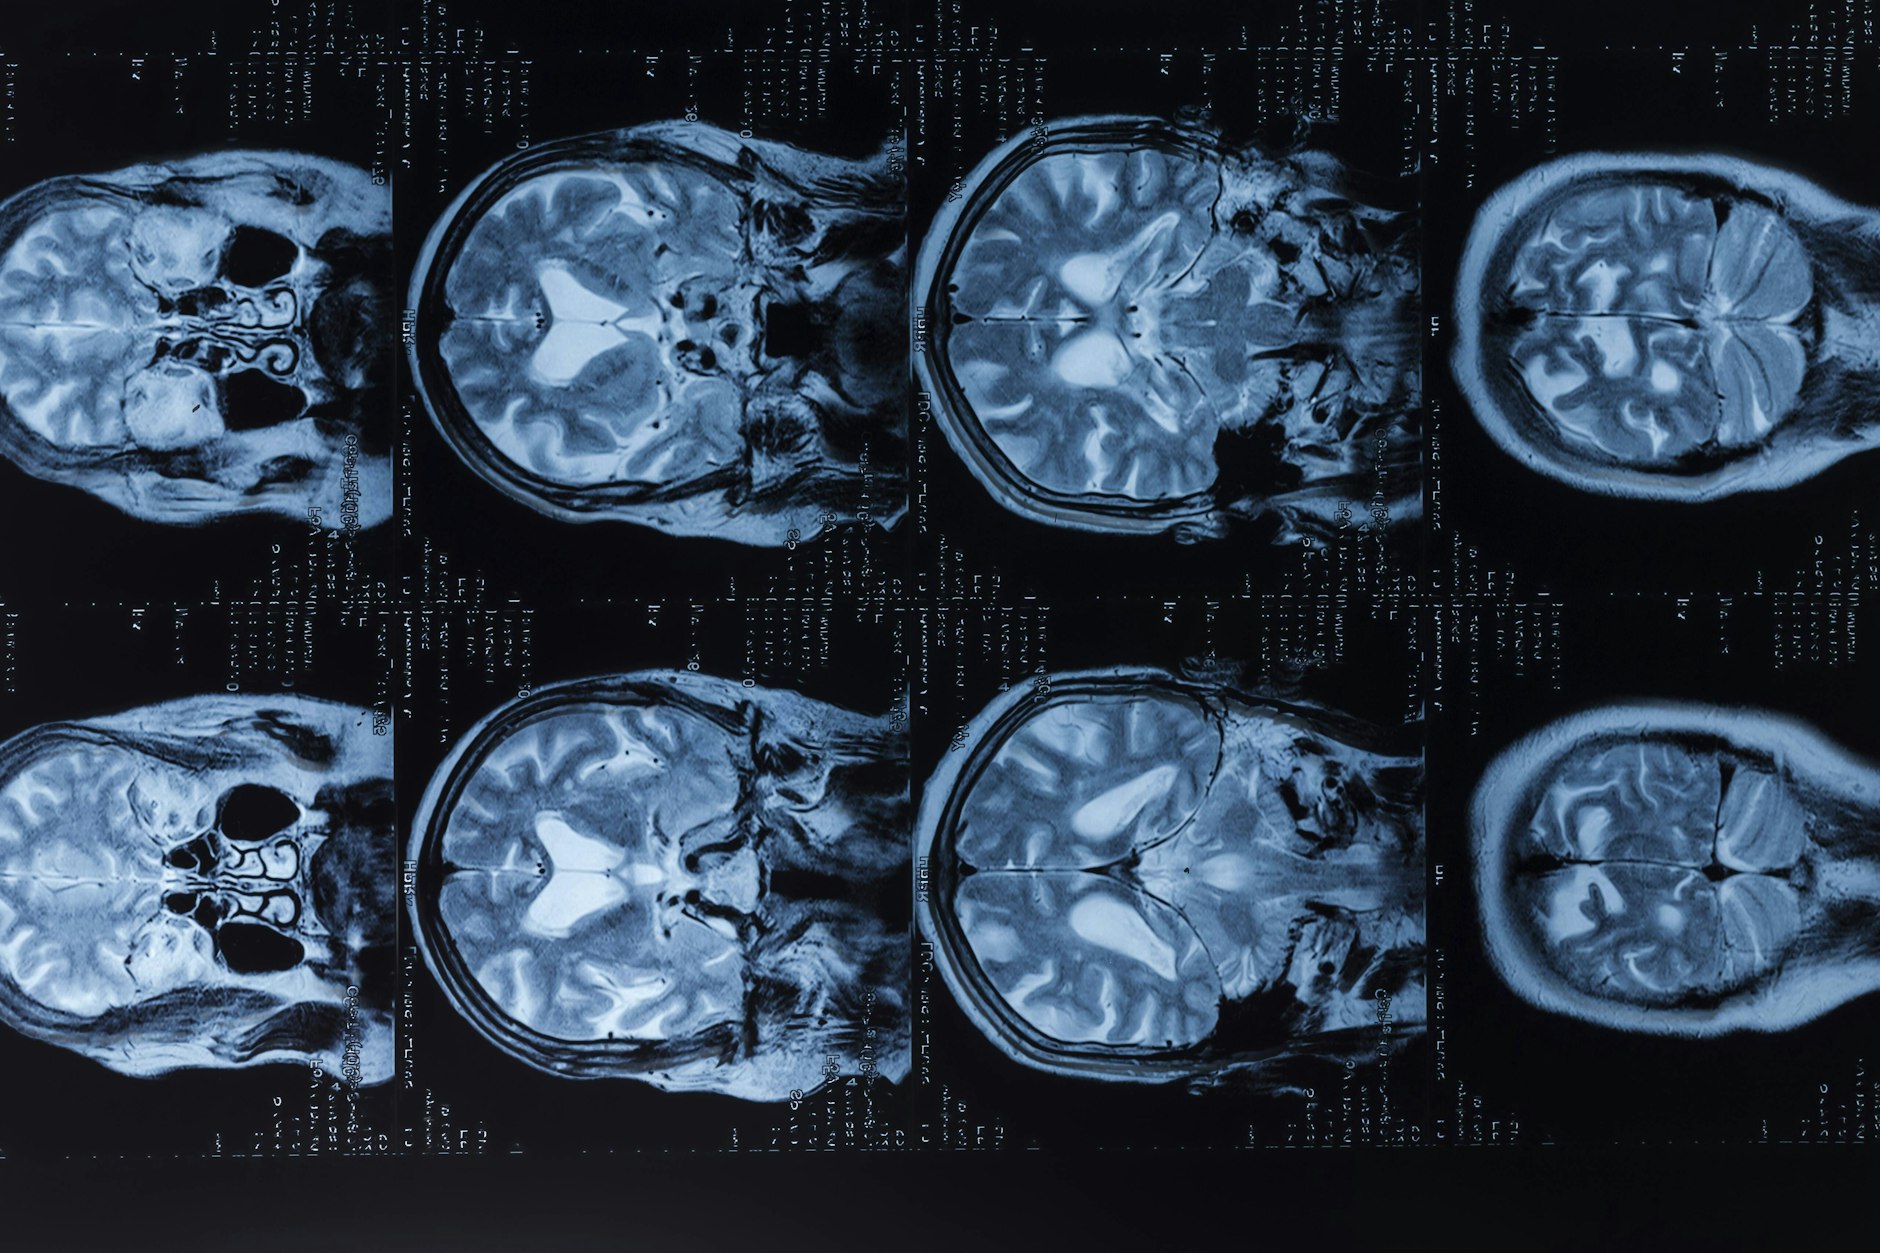

MRT vom Kopf: „Sogar die Markrinde war betroffen“

Die Tochter wurde weiter untersucht. „Sehr spät erst diagnostizierten die Ärzte schließlich eine Enzephalitis.“ Die Gehirnentzündung war mittlerweile weit fortgeschritten. „Die Markrinde war schon betroffen“, sagt Regina Hünecke. Sie hat ein MRT vom Kopf, das den Befund belegt, eine Aufnahme aus jenen Tagen und zum Vergleich sogar ein MRT, das vorher entstanden war. „Da erkennt man deutlich den Unterschied. Auf der zweiten Aufnahme sehen die Konturen des Gehirns verwaschen aus.“